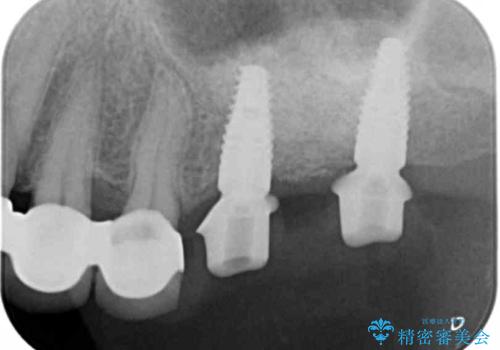

- 80万円(ストローマンインプラント×2・チタンカスタムアバットメント×2・ジルコニアクラウン×2)費用は治療当時の料金となります

力学的に無理のある遊離端ブリッジをインプラントを用いて長期的な予後を見込める補綴状態へと改善しました。